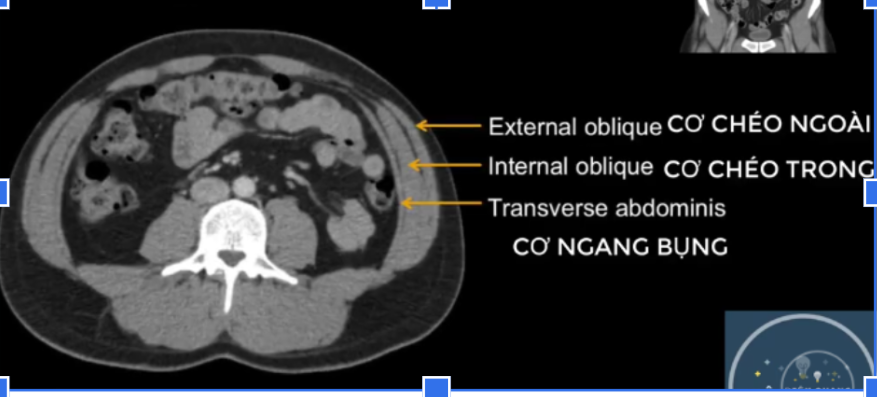

cơ chéo ngoài? trong? ngang b?